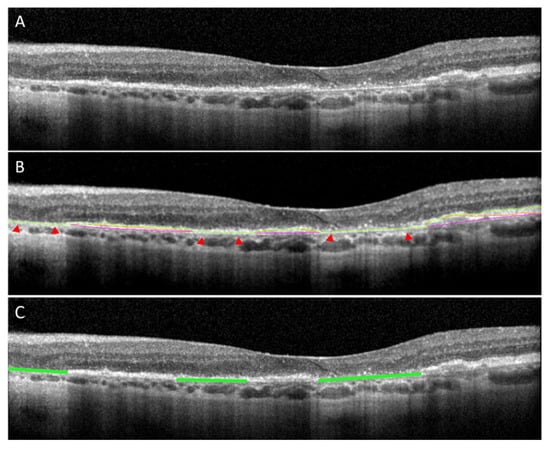

2.2. Retinal Layers Ground Truth

2.3. GA Ground Truth Mask Generation for B-Scan Model

3.1. The B-Scan Cross-Sectional GA Detector and Quantifier